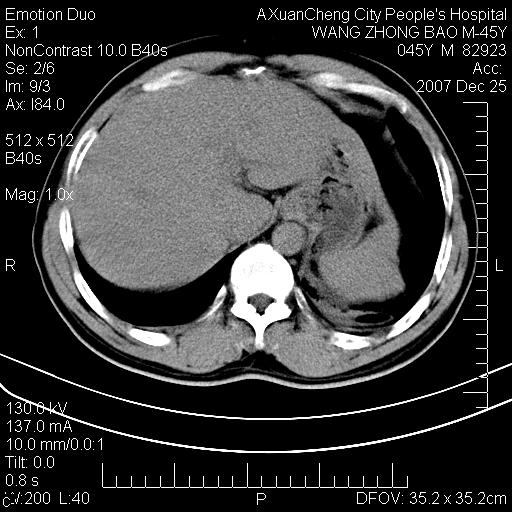

以下是引用qiuleiyu在2007-12-25 18:14:00的发言:[br]胰腺增大,周边渗出改变,肾前筋膜明显增厚,示少量积液.胆囊壁毛糙,周边少许渗出,胆总管壁厚,异常强化,然扩张不明显.结合病程急短;考虑;胆管炎,胆囊炎,胆源性胰腺炎可能大,请结合实验室检查及随访.

以下是引用lisihao在2007-12-25 14:23:00的发言:[br]急性水肿型胰腺炎[br]依据:1、胰腺弥漫性肿大,边缘稍毛糙;[br] 2、双侧肾周筋膜增厚,尤以左侧为甚(重要征象)[br] 3、双侧后胸膜增厚(刺激性炎症);[br] 4、结合病史,查血尿淀粉酶应该可以确诊。